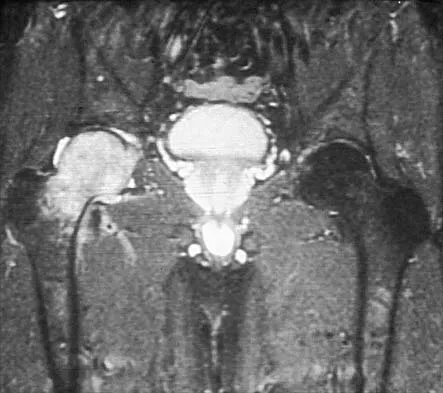

A 58-year-old woman with a metal-on-metal total hip arthroplasty performed 9 years ago presents with new-onset groin pain and a palpable mass. Radiographs show an acetabular component positioned in 55 degrees of abduction. Serum cobalt levels are markedly elevated. An MRI with metal artifact reduction sequence (MARS) demonstrates a solid and cystic mass communicating with the joint space. What is the characteristic histopathological finding associated with this mass?